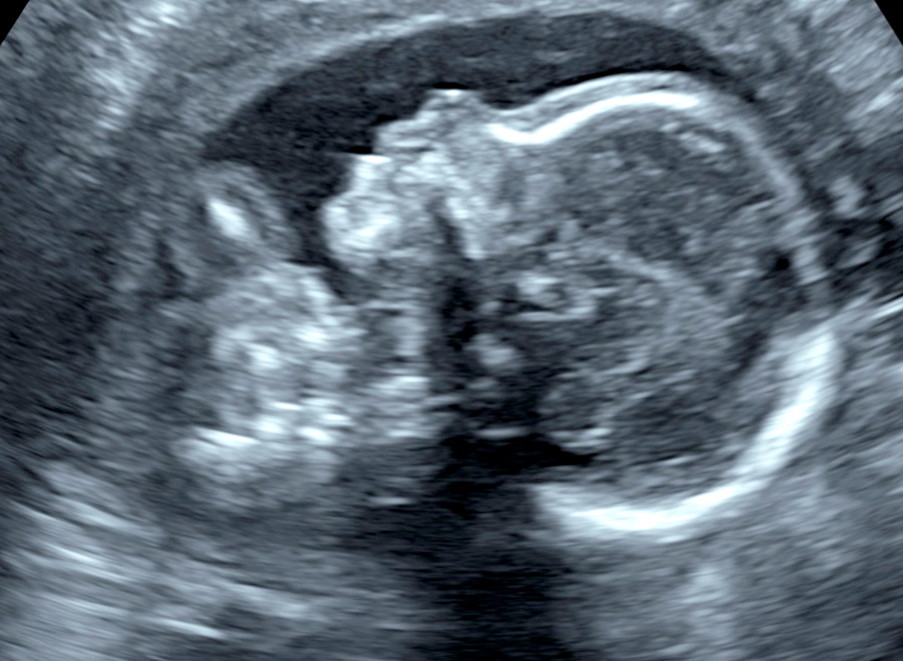

Since I don’t think I mentioned it here: our tiebreaker baby is a boy!

This will bring us to five boys, four girls — with three boys in a row at the end (so far). I keep thinking what our homeschool will look like five years from now, with three little boys in elementary school! I imagine a bit different than it does now. 🙂 Other good news: baby is measuring right on track despite my feeling gigantic. I keep telling myself that this is my ninth baby, so my looking nine months pregnant at only six isn’t a huge surprise. And that, like last time, I hit my biggest point a bit earlier than normal and then just kind of hang out with that belly until the end. (Right? I hope so.)

He is moving quite a lot these days — all the siblings have had a chance to feel his kicks from the outside. Drew camps out at my side with his hand resting on my tummy, waiting for kicks!